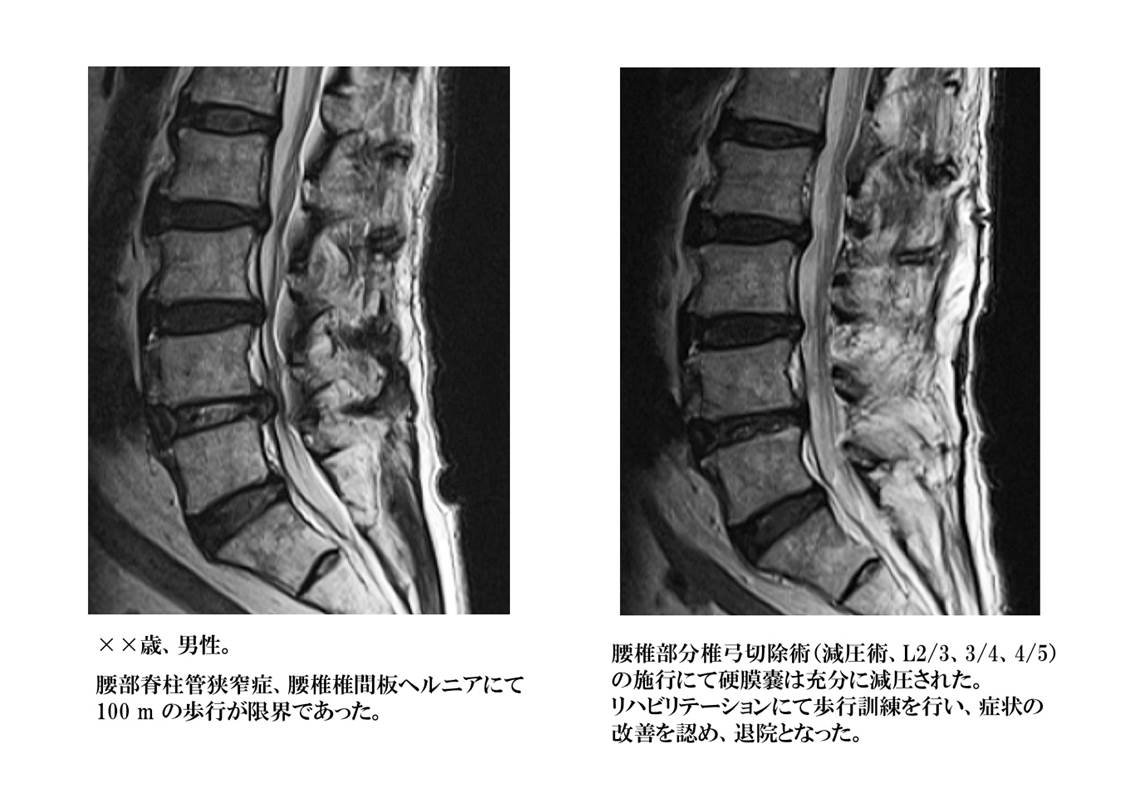

脊柱管狭窄症

背骨の内部にある脊髄が通る部分を脊柱管と呼びます。長期間に及ぶ頚部、腰部への負担により椎体などの骨が変形したり、後方の椎弓と呼ばれる骨の間に存在している靱帯(黄色靱帯)が厚くなったりする(肥厚)ことにより、脊柱管が狭くなり、脊髄が圧迫されている状態です。脊髄周囲の隙間(くも膜下腔と言います)が狭くなり、脊髄が背骨の内部で窮屈な状態が続くと血液の通いも悪くなり、脊髄自体の働きが低下してくる可能性があります。

腰椎に発生した場合には、下肢のしびれ感、感覚低下、歩行困難などの症状を良く見かけます。それまでは問題なく歩けていた距離が歩けなくなったり(横断歩道が渡りきれなくなったり)、長距離の歩行中に腰部や下肢が痛くなり休憩が必要になるなどの症状は典型的な腰部脊柱管狭窄症の症状です。

減圧術

脊髄、神経は周囲を骨組織、靱帯、椎間板などにて囲まれているので、圧迫の原因となるのも周囲にある組織です。圧迫の場所、方向、程度などにて、手術の方法が決定されます。通常は前方及び後方から皮膚を切開して、脊椎周囲の筋肉の隙間を分け入り、必要最小限の骨組織を削除した後に、脊髄・神経を包んでいる硬膜を圧迫している原因病変を削除、摘出します。

椎間板ヘルニア、変形性頚椎症、脊柱管狭窄症、靱帯骨化症、アーノルド・キアリ奇形(I型)、末梢神経絞扼性疾患など、適応となる疾患は非常に多く、脊椎・脊髄疾患に対する外科治療の中で最も良く行われる手術法です。近年は如何に小さな皮膚の切開で治療を行うか、如何に脊椎周囲の筋肉の剥離を最小限に止めるか、如何に骨の削除範囲を少なくするかを考え、低侵襲での外科治療法が発達してきています。